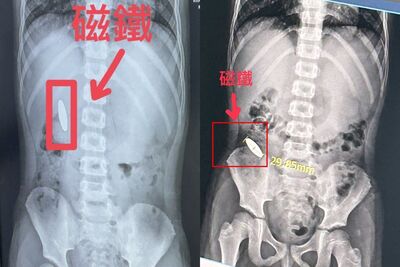

台南市安南區1月27日下午發生一起離譜事件!一名小一學生在補習班遭小五學長逼吞下長達3公分長的磁鐵,而補習班並未主動通報教育局,受害家長事發兩天後傳簡訊告訴國小導師,全案因此曝光,該補習班同時被查出3項違規,社會局、教育局將依法處置。 《詳全文...》